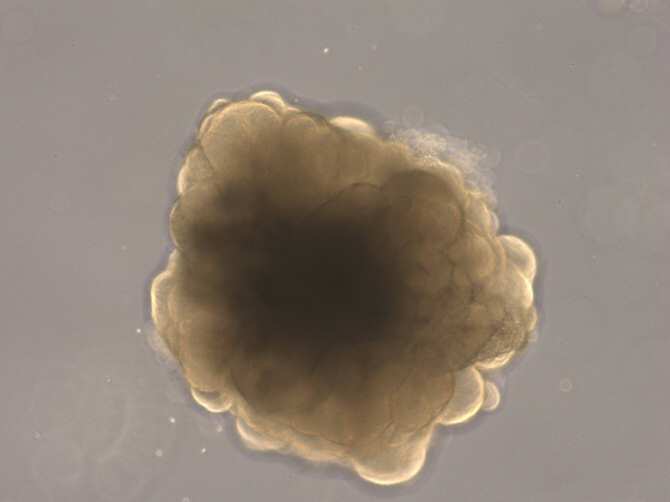

Para evitar en lo posible los experimentos con animales, se utilizan como alternativa los organoides cerebrales. Estas estructuras celulares tridimensionales, de unos pocos milímetros de tamaño, reflejan distintas etapas del desarrollo cerebral y pueden modificarse genéticamente.

Organoide de cerebro de un mono macaco rhesus. (Foto: Nesil Eşiyok)

El equipo de Lidiia Tynianskaia y Michael Heide, ambos del Centro Alemán de Primates, ha conseguido ahora manipular genéticamente organoides cerebrales de forma rápida y eficaz. El procedimiento requiere solo unos días en vez del plazo habitual de varios meses y puede utilizarse para organoides de diferentes especies de primates.